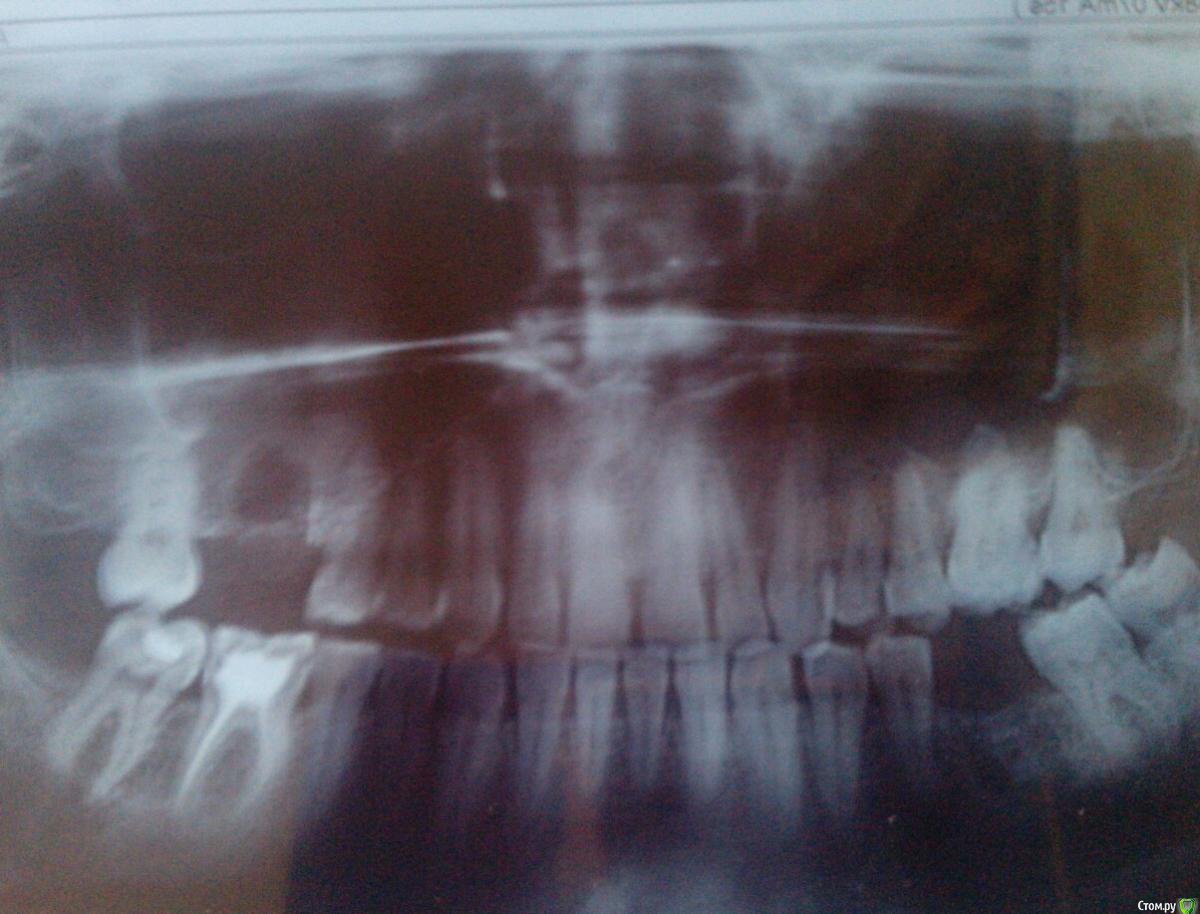

leshui78 Опубликовано 18 марта, 2016 Автор Поделиться Опубликовано 18 марта, 2016 (изменено) Добрый день уважаемые врачи и форумчане. Моя печальная история сейчас продолжается в больнице в лор-отделении. Вчера мне была проведена операция радикальная гайморотомия. С превеликим удивлением хирург оперироваваший меня, извлек из гайморовой пазухи огромный тампон. Тампон оставили там ,когда доставали остаток корня. Он все это время там гнил и разлагался. Когда я очнулся от наркоза, первые слова доктора : - Мы вас спасли !!! Фото с вчерашней операции прилагаю. Тампон лежит у меня на животе. Ода халатным и криворуким врачам той клиники !!!!! Изменено 18 марта, 2016 пользователем leshui78 1 Ссылка на комментарий

leshui78 Опубликовано 18 марта, 2016 Автор Поделиться Опубликовано 18 марта, 2016 (изменено) Она, наверное...Нет . Турунду мне изьяли перед снятием швов, она была поверхностная и крепилась к соседним зубам. А тампон оказался зашитым внутри .Когда меня оперировали , зловоние от скопившегося в пазухе гноя, стояло такое, что хирурги в последствии одели специальные маски.Фото я их не просил делать, они были в шоке от увиденного и поэтому сфотографировали. Изменено 18 марта, 2016 пользователем leshui78 Ссылка на комментарий